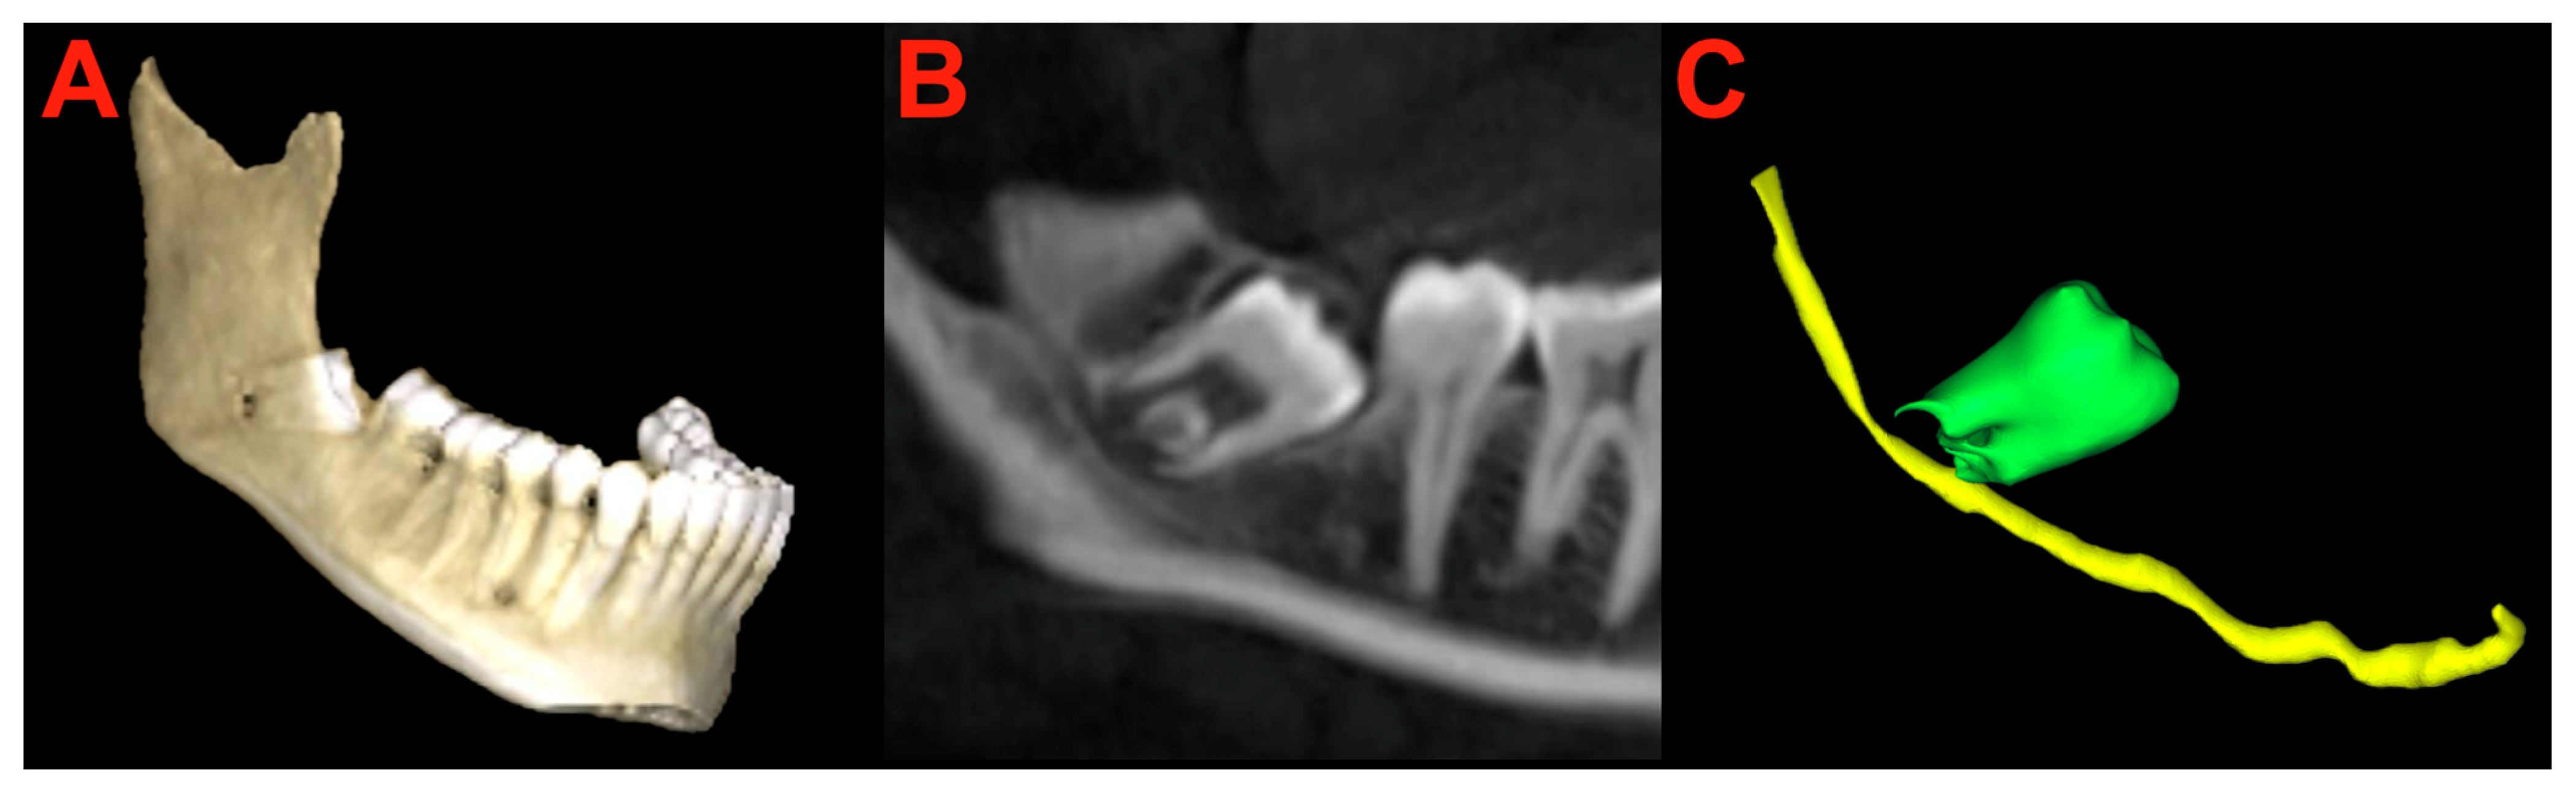

1. Introduction

2.3. Clinical Patients

2.6. Segmentation and Preparation

2.7. Surgery